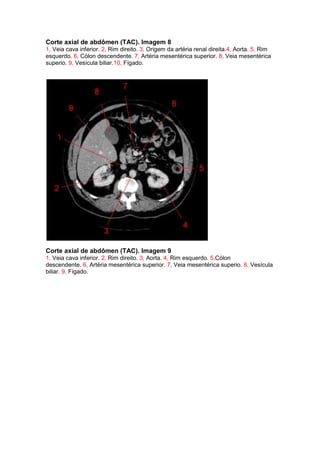

Corte axial de abdômen (TAC). Imagem 8

1, Veia cava inferior. 2, Rim direito. 3, Origem da artéria renal direita.4, Aorta. 5, Rim

esquerdo. 6, Cólon descendente. 7, Artéria mesentérica superior. 8, Veia mesentérica

superio. 9, Vesícula biliar.10, Fígado.

Corte axial de abdômen (TAC). Imagem 9

1, Veia cava inferior. 2, Rim direito. 3, Aorta. 4, Rim esquerdo. 5,Cólon

descendente. 6, Artéria mesentérica superior. 7, Veia mesentérica superio. 8, Vesícula

biliar. 9, Fígado.

Corte axial deabdômen (TAC). Imagem 8 1, Veia cava inferior. 2, Rim direito. 3, Origem da artéria renal direita.4, Aorta. 5, Rim esquerdo. 6, Cólon descendente. 7, Artéria mesentérica superior. 8, Veia mesentérica superio. 9, Vesícula biliar.10, Fígado. Corte axial de abdômen (TAC). Imagem 9 1, Veia cava inferior. 2, Rim direito. 3, Aorta. 4, Rim esquerdo. 5,Cólon descendente. 6, Artéria mesentérica superior. 7, Veia mesentérica superio. 8, Vesícula biliar. 9, Fígado.